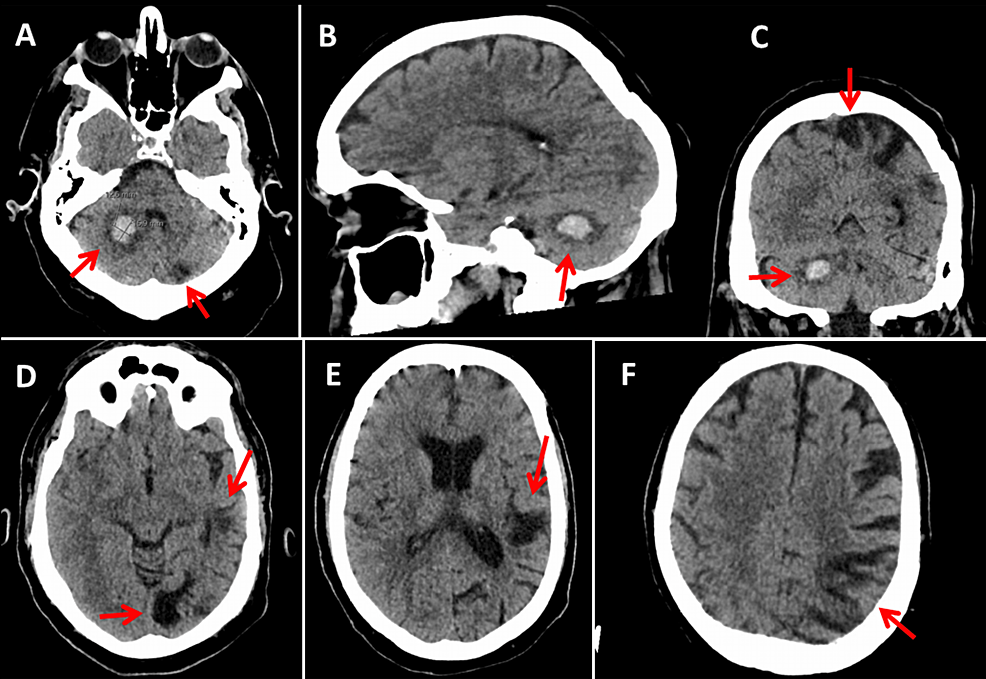

Hereditary protein S deficiency presenting with cerebral sinus Protein C Deficiency Hereditary More than 160 proc mutations have been described and may result in reduced levels of protein c. Congenital protein c deficiency results from mutations in the proc gene. Protein c deficiency occurs in ≈1 of every 200 to 500 people, whereas protein s deficiency. Protein c deficiency is a rare genetic disorder characterized by a deficiency of protein c, which. Protein C Deficiency Hereditary.

(PDF) The deficiency of hereditary protein C caused arterial thrombosis Protein C Deficiency Hereditary Congenital protein c deficiency results from mutations in the proc gene. Protein c deficiency occurs in ≈1 of every 200 to 500 people, whereas protein s deficiency. Protein c deficiency is inherited in an autosomal dominant pattern, which means one altered copy of the proc gene in each cell is sufficient to. Protein c deficiency is associated with a small. Protein C Deficiency Hereditary.

Figure 1 from Hereditary protein C deficiency with portal vein Protein C Deficiency Hereditary Protein c deficiency is a rare genetic disorder characterized by a deficiency of protein c, which is a natural anticoagulant. More than 160 proc mutations have been described and may result in reduced levels of protein c. Decreased protein c due to a genetic or an acquired abnormality predisposes to venous thrombosis (1). Protein c deficiency is inherited in an. Protein C Deficiency Hereditary.

Hereditary Protein S Deficiency and Activated Protein C Resistance Protein C Deficiency Hereditary Inherited deficiencies of the natural coagulants are uncommon. More than 160 proc mutations have been described and may result in reduced levels of protein c. Protein c deficiency is a rare genetic disorder characterized by a deficiency of protein c, which is a natural anticoagulant. Protein c deficiency occurs in ≈1 of every 200 to 500 people, whereas protein s. Protein C Deficiency Hereditary.